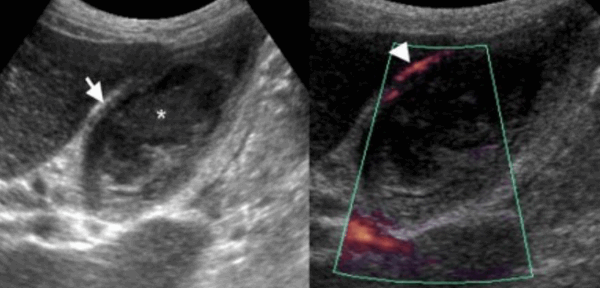

Острый бескаменный холецистит возникает у пациентов во время поста, а также у пациентов, которые принимают лекарства, вызывающие холестаз. К признакам некалькулезного холецистита относятся все признаки острого калькулезного холецистита кроме наличия камней в просвете желчного пузыря, но при этом взвесь обычно присутствует.

74 — летнему мужчине выполнено УЗИ желчного пузыря. Диагноз: острый некалькулезный холецистит. На левой сонограмме стрелкой указано утолщение стенок желчного пузыря. В просвете желчного пузыря взвесь. На правой сонограмме у того же пациента при исследовании в доплеровском режиме выявлен еще один признак воспаления — гиперемия.